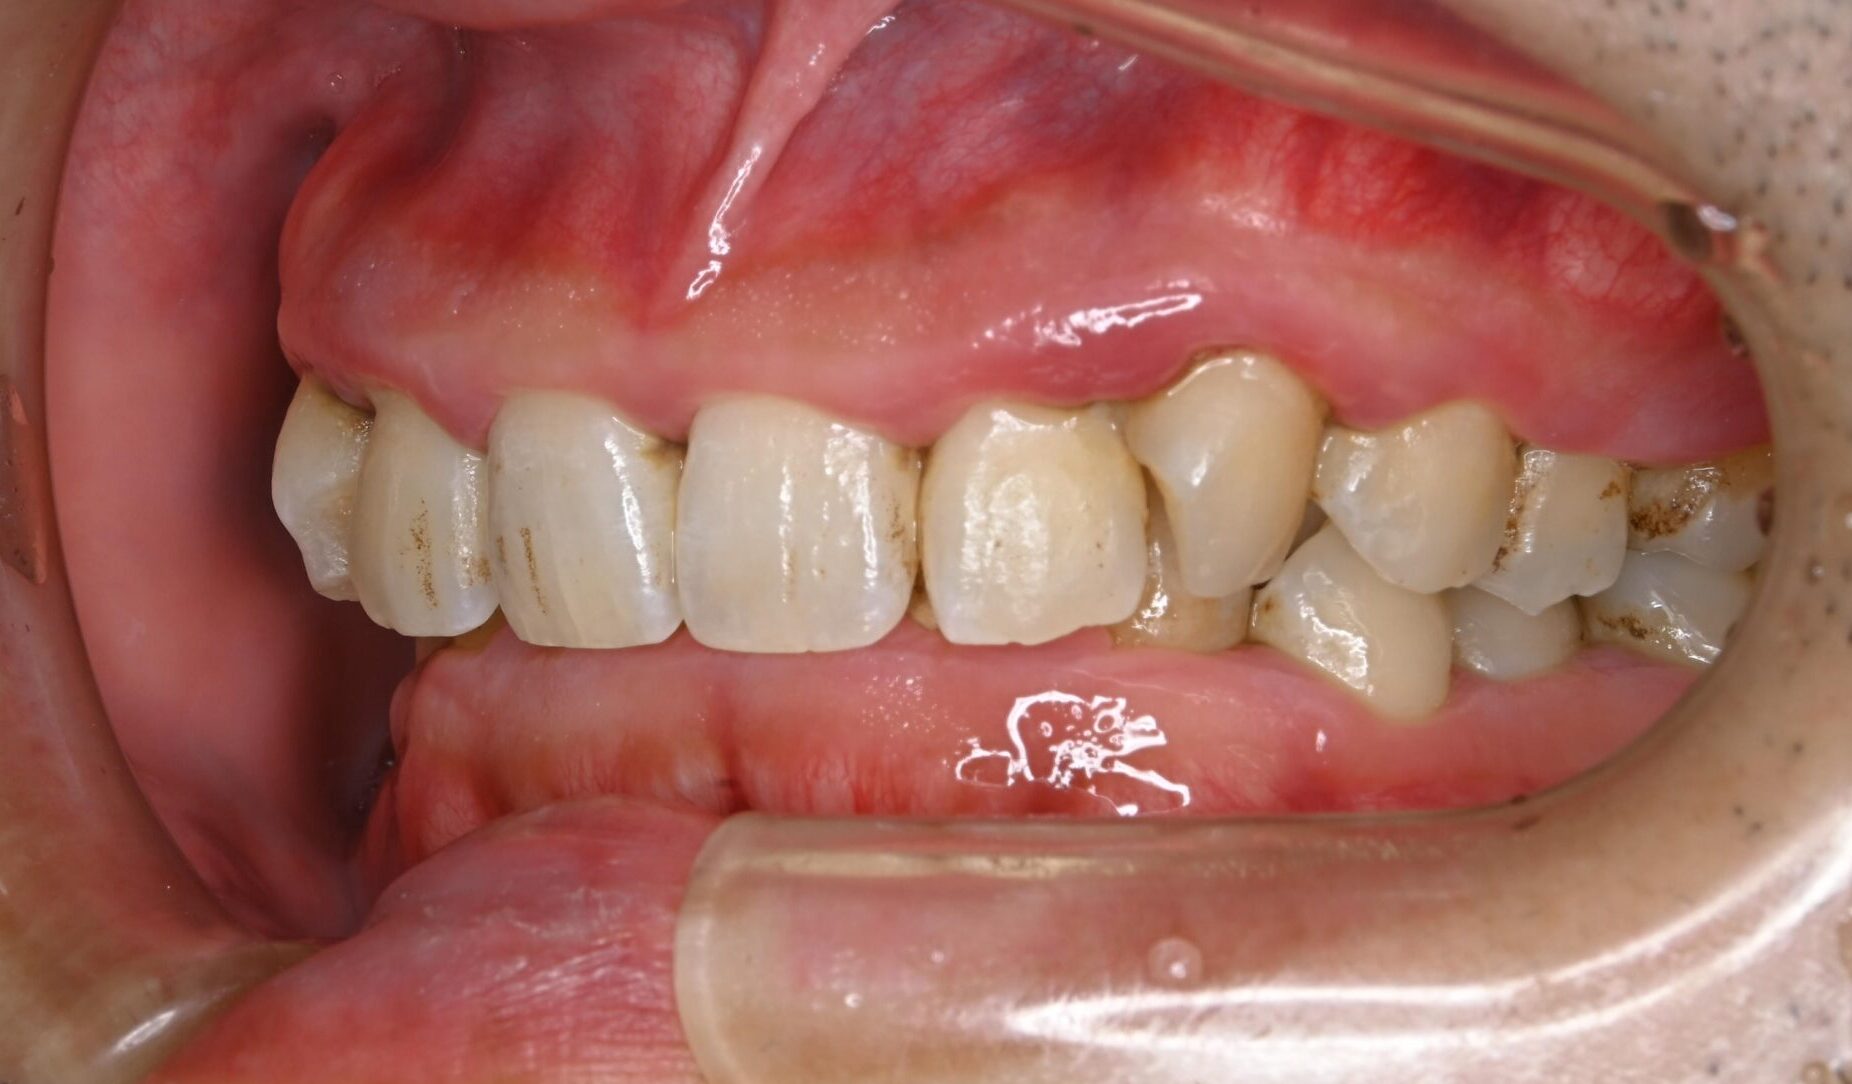

30代・男性

歯茎から出血、歯石除去|中等度に進行した歯周病

症例写真 before

中等度歯周病

歯医者が久しぶりなのでクリーニングをしてほしい、ということで来院されました。

レントゲン撮影、歯周検査などを行なった結果、全体に多くの歯石付着が認められる進行した中等度の歯周病であることが判明しました。ご本人も歯茎から出血することは気になっており、担当歯科衛生士から歯周病について説明を行いました。

今回は歯石の付着が広範囲に渡っており量も多いことから、歯科衛生士による歯周基本治療に加え歯科医師による外科手術も行うことで、徹底的に治療していくことになりました。